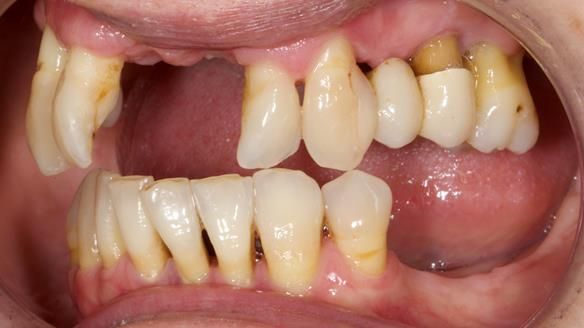

She had previously suffered from generalised periodontitis – stage IV, grade C, currently stable, with reduced attachment across the upper arch.

By the time she came to me, her periodontal condition was stable — but the aesthetics in the upper jaw were very poor.

- Her upper jaw had insufficient bone and would have required significant augmentation.